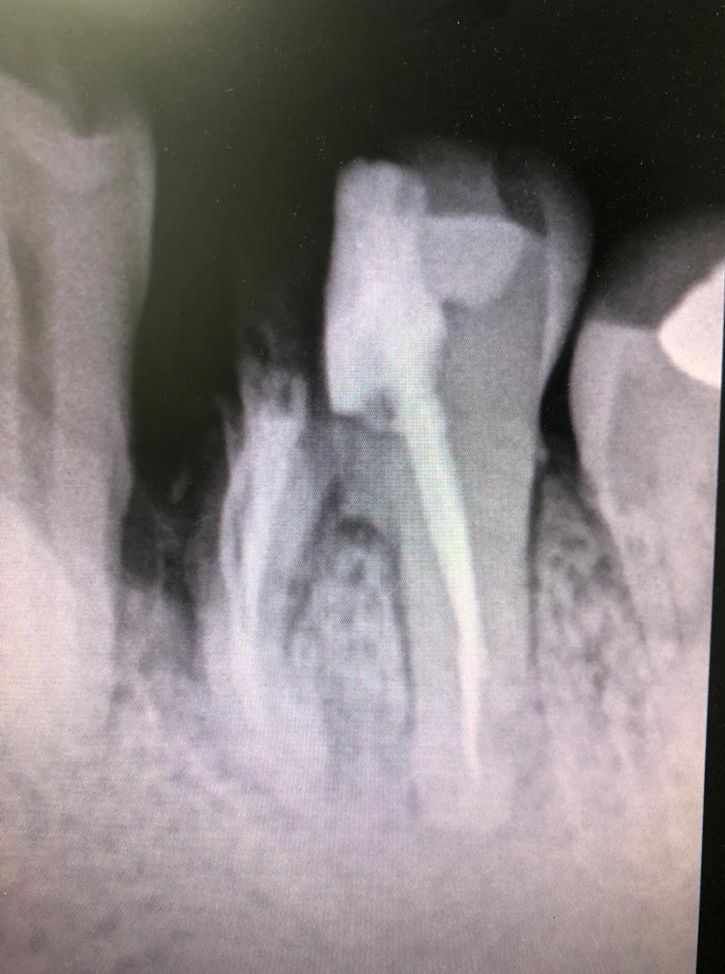

Pasado un tiempo se le cita para tallar el muñón de la raíz distal, que ha tenido una buena evolución una vez separada de la raíz anterior infectada.

En la misma sesión se le instala el hilo de retracción, para la toma de impresiones con siliconas. También diseñamos una corona de circonio multilayer, la cual se le cementa al cabo de una semana. Esta corona de circonio se deja muy suave de oclusión para que no sea presionada por las fuerzas de masticación y bruxismo, porque tendría más tendencia a la fractura.

También hay que insistir al paciente en la higiene, pues hay que limpiar la zona con hilo de seda dental metiéndose por debajo de la zona coronal que está en extensión protética. Se cita al paciente para revisiones periódicas.